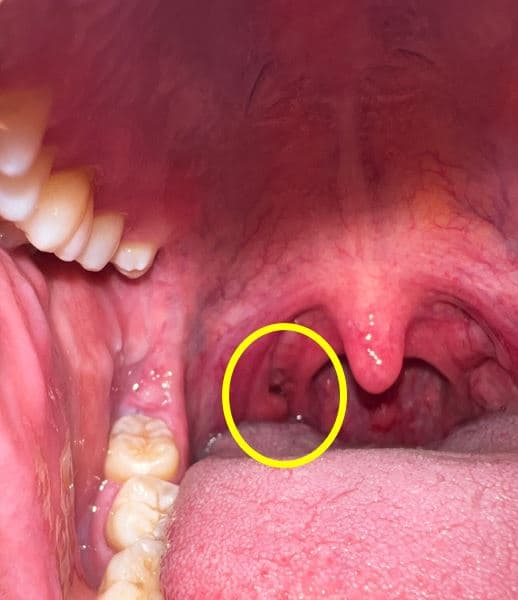

어느순간부터 편도쪽에 이질감과 함께 편도결석의 악취가 느껴져 핸드폰으로 촬영을 해봤습니다.

확인결과 목구명 편도 쪽에(아래사진의 목구멍편도 좌측 구멍) 구멍이 있습니다.

이상없을까요 ?